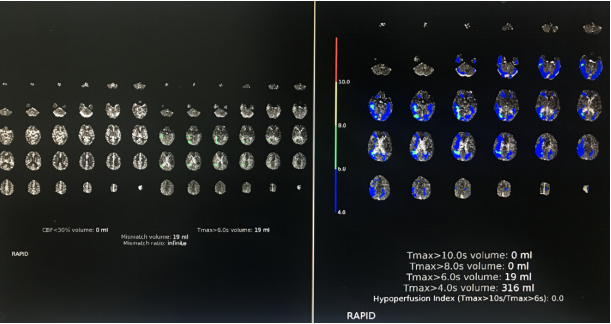

手术前检查:

2019-5-15 CTA提示右侧MCA-M1段重度狭窄,狭窄远端近分叉部血管略有扩张

CTP提示Tmax>6s 19ml

复查CT灌注,可见MCA供血区域远端血流较术前明显变差